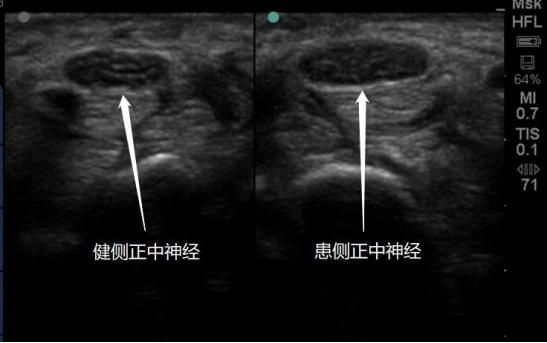

超声影像显示双侧正中神经对比

“腕管综合征”俗称“鼠标手”。多数病因是因为手和腕长期过度使用,引发慢性炎症损伤,导致“腕管”这个神经、肌腱等组织经过的“隧道”相对变窄,道路拥挤,神经被卡住发炎,自然就会感觉腕部疼痛、手指麻木无力,属于神经卡压综合征的一种。临床上常见的神经卡压综合征还有腕部尺管综合征、肘管综合征等。